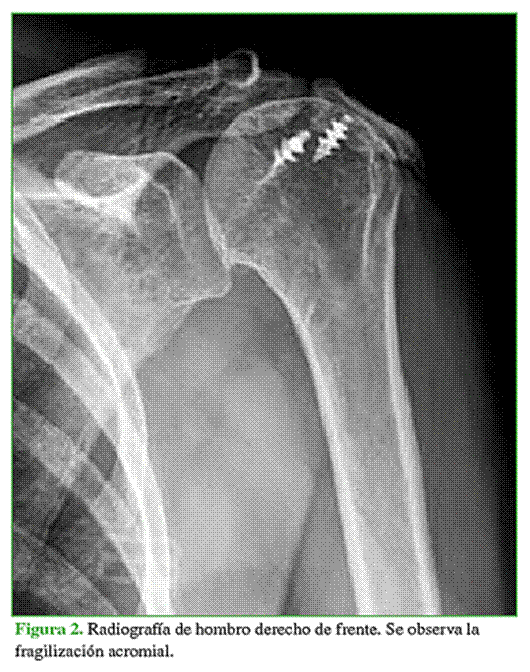

La tasa de complicaciones fue del 12,5% (5 casos). Cuatro fueron intraoperatorias (2 complicaciones menores y 2 mayores). Dos complicaciones menores (5%) fueron una fractura glenoidea que requirió la colocación de una glena de revisión en el mismo acto quirúrgico, sin que esto afectara el resultado obtenido. Una paciente sufrió dos complicaciones mayores. Se trató de uno de los primeros casos de nuestro Centro, en el comienzo de la curva de aprendizaje. La paciente sufrió una fractura periprotésica intraoperatoria de la diáfisis humeral, sintetizada con cerclajes y tratada con un brace, que evolucionó con neuropraxia del nervio radial y resolución parcial. Otra paciente evolucionó con un cuadro de insuficiencia acromial, debido a una fragilización acromial preoperatoria que repercutió en el rango de movilidad (Figura 2).

En esta serie, una paciente presentaba fragilización acromial preoperatoria, lo cual repercutió desfavorablemente en el rango de movilidad máximo a la elevación anterior, era solo de 90° en el último control posoperatorio. Este resultado se puede explicar teniendo en cuenta que la inserción acromial del deltoides es un elemento clave en la función de la AI.15 El descenso y la medialización del centro de rotación glenohumeral con el objetivo de restaurar la tensión deltoidea son fundamentales para mejorar la elevación anterior activa. Se ha propuesto que la patología acromial preoperatoria puede comprometer la función deltoidea y afectar el correcto funcionamiento de la prótesis, a diferencia de Walch y cols., quienes evaluaron a 28 pacientes con AMR tratada mediante AI y con patología acromial, y compararon los resultados funcionales con los obtenidos en pacientes sin lesión acromial. Estos autores no hallaron diferencias en el rango de movilidad posoperatorio y el puntaje de la escala de Constant-Murley.28